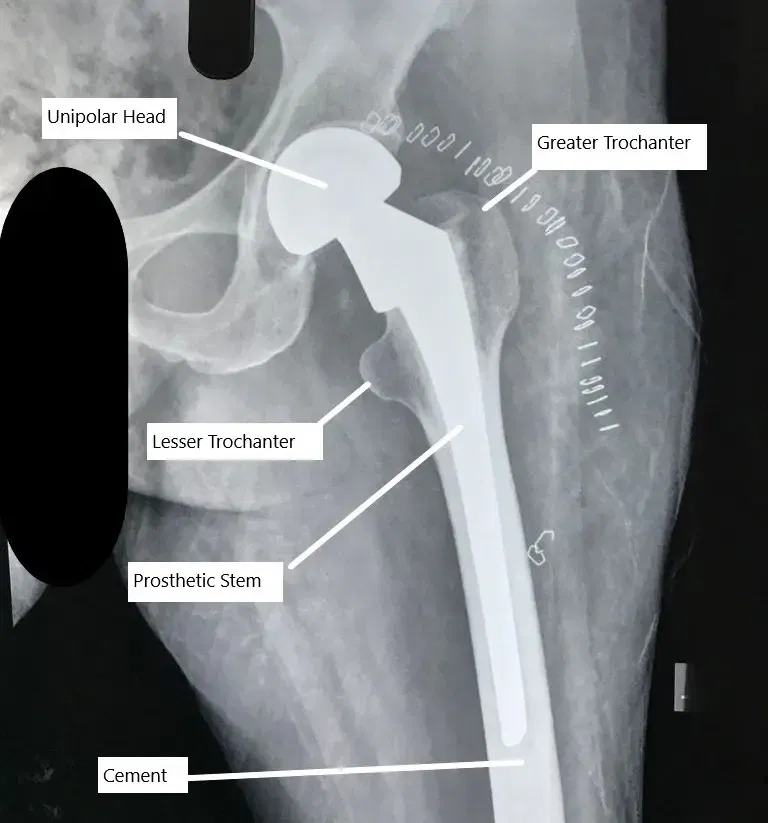

Partial unipolar hip replacement X -ray

Compared to bipolar, a unipolar partial hip replacement only consists of a head firmly attached to the stem of the prosthesis. The bipolar design provides greater stability, movement and also helps protect the articular cartilage. The ball in ball design mimics the socket of the total hip replacement.